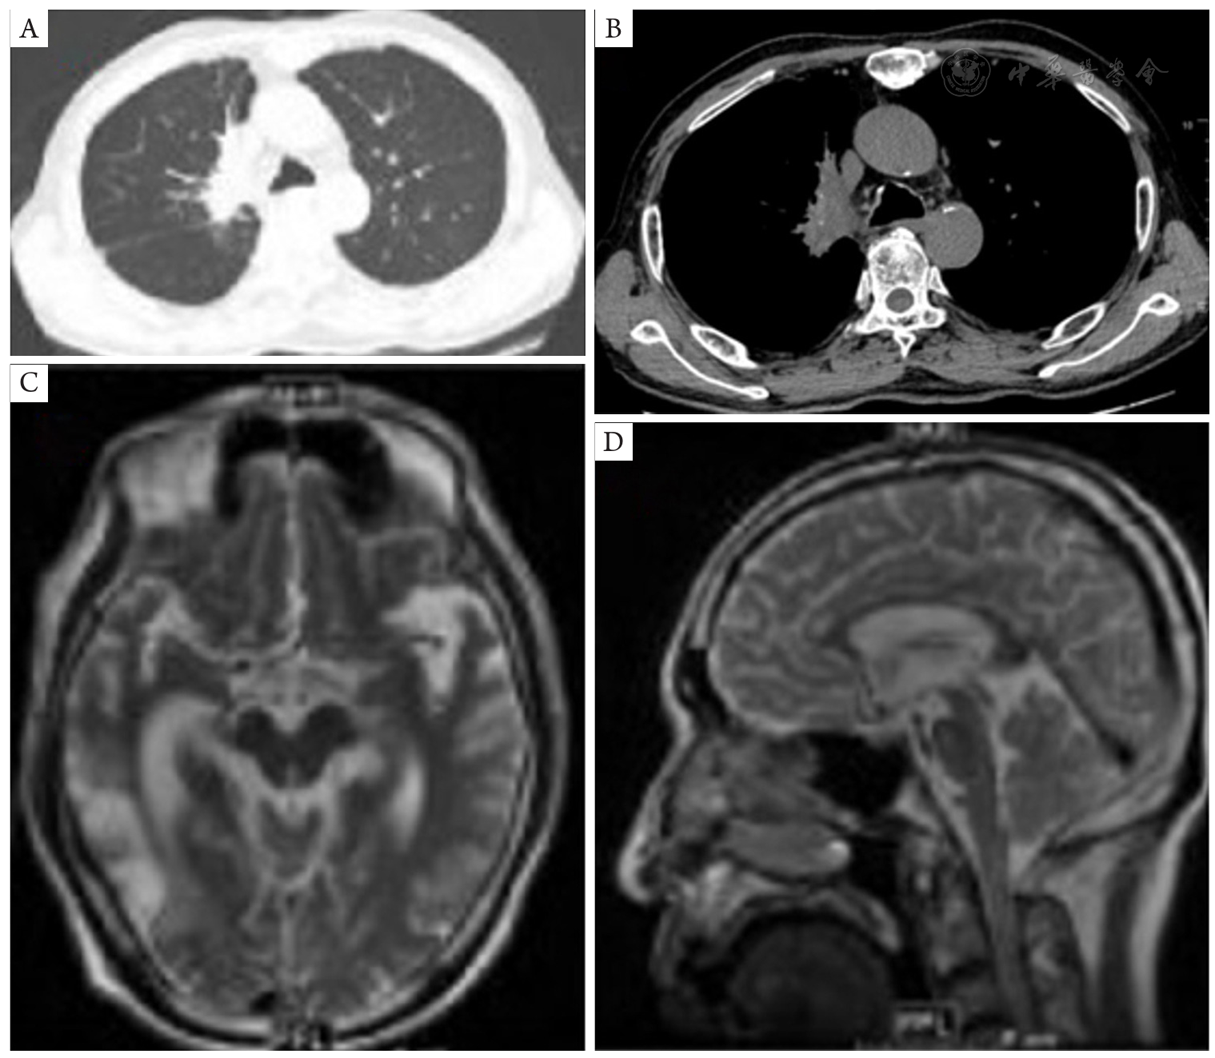

图3 患者2年后我院门诊复查胸部强化CT及头颅MRI平扫情况。A,B:胸部强化CT示右肺上叶及右肺门区病变,最大横截面积约62 mm × 32 mm;C,D:头颅MRI示右侧颞枕叶、左侧顶叶病灶局限。CT:计算机断层扫描;MRI:磁共振